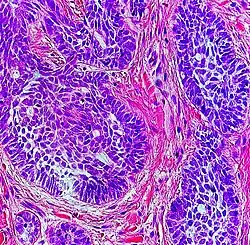

Architectural pattern of any suspicious cells, in this case nests of cells, as well as components of the intervening stroma.

Architectural pattern of any suspicious cells, in this case nests of cells, as well as components of the intervening stroma. -